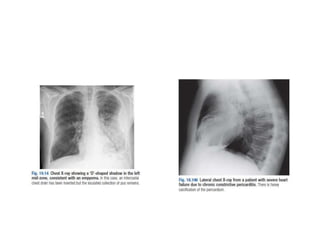

• Figure 10.17

• Chest X-ray showing a

large left pleural effusion

in a young man with a 4-

month history of malaise,

fever, night sweats and

weight loss. The diagnosis

of tuberculosis was

confirmed on histology of

a pleural biopsy and

culture of the pleural

fluid.